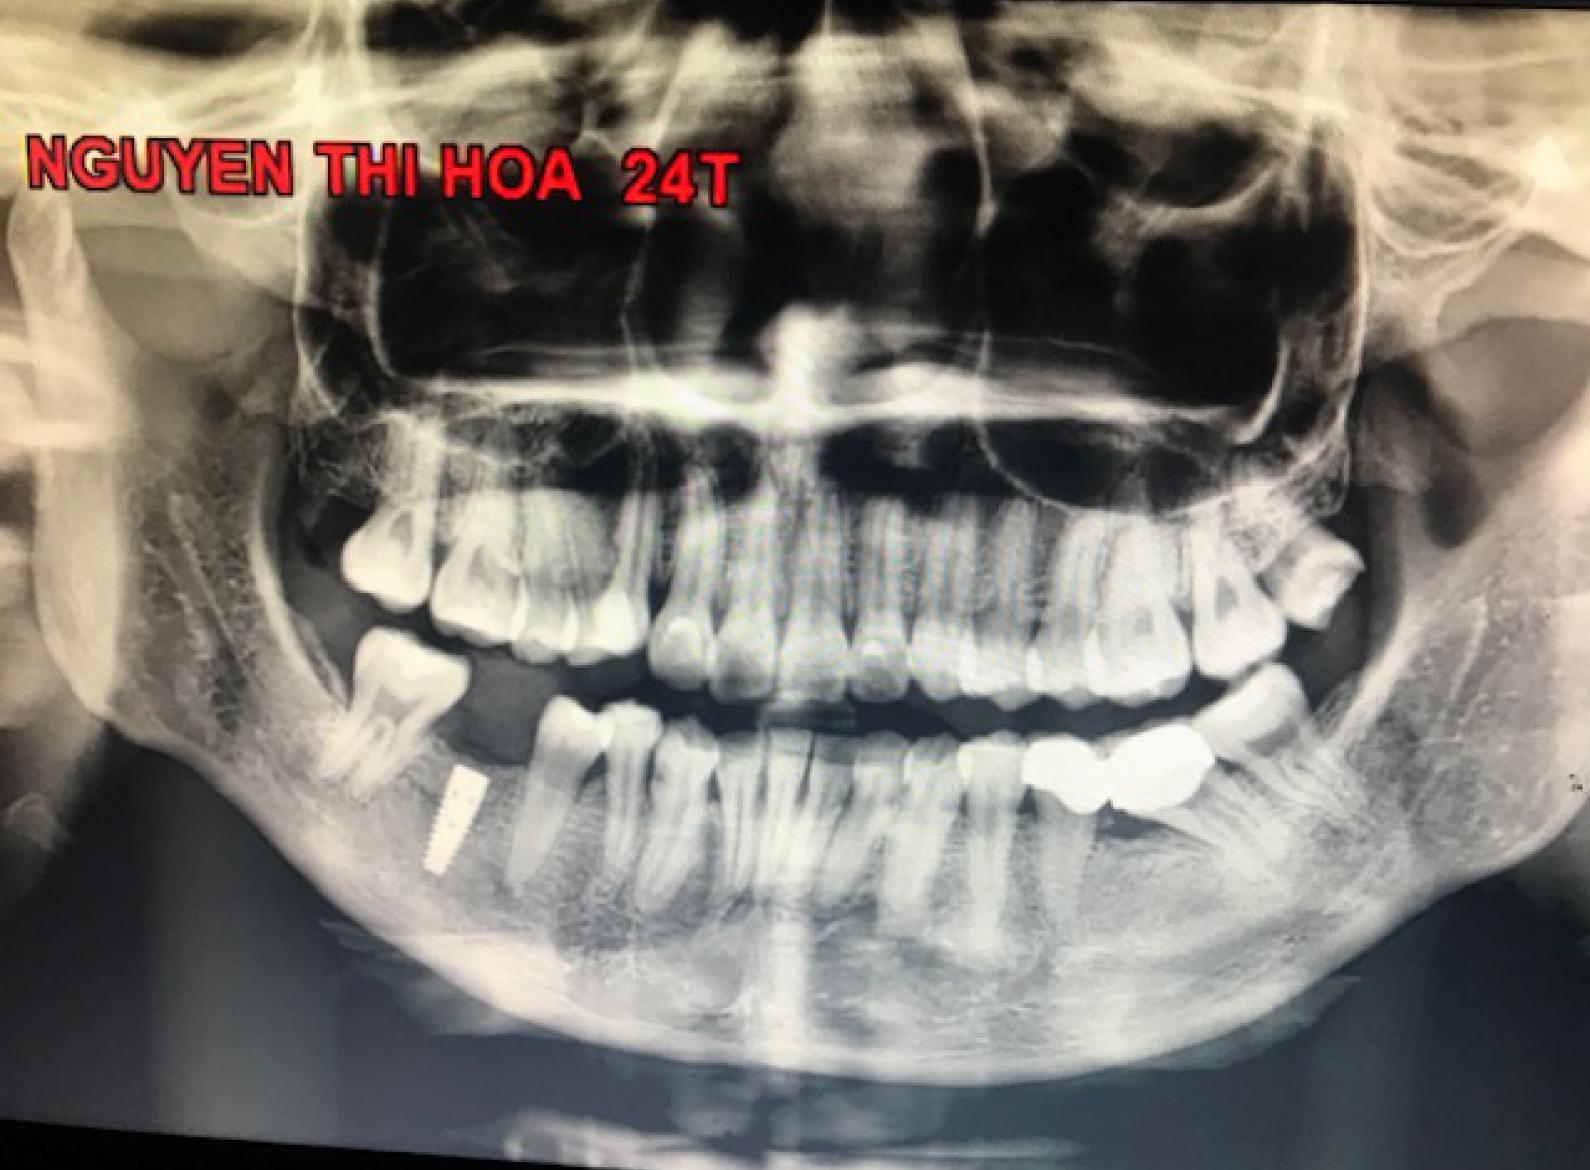

Cấy răng nha khoa (hay cấy ghép Implant) là phương pháp thay thế răng đã mất bằng cách cấy một trụ kim loại (trụ implant) bằng titan vào xương hàm, sau đó gắn mão răng sứ lên trên để tạo thành một

Công nghệ cấy ghép răng Implant nha khoa thế hệ 4S là giải pháp phục hồi răng mất hoàn hảo, bao gồm cả thân răng sứ và trụ chân răng Titanium – Zirco bền vững, với chức năng và thẩm mỹ giống như răng